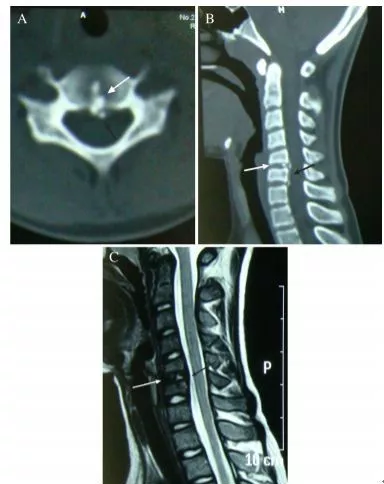

40歲男性,低熱伴急性頸痛、張口困難1天,頸椎CT提示椎前鈣化(箭頭),經洛索洛芬60mg,每日三次,連續五天治療,3天后症狀改善,3月複查CT鈣化消失。(PMID: 25918175)

32歲男性,頸肩部疼痛1月,喝水時輕度吞嚥困難伴頸椎活動受限,無發熱,化驗指標正常,經非甾體抗炎藥和秋水仙鹼治療後症狀改善,4月後複查頸椎側位片(D,E)鈣化消失。(PMID: 25941110)

30歲女性,診斷為頸長肌鈣化性肌腱炎,但鈣化位於不尋常的位置:C4-5椎間隙前側。A:頸椎側位片示寰樞椎半脫位(長箭頭)和椎前軟組織腫脹(無線箭頭);B,C和D:頸椎MRI示C1-6椎前軟組織腫脹伴積液,D示齒狀突骨侵蝕(無線箭頭)

上述病人,E為增強,F為抑制像,G和H:經非甾體抗炎藥治療3天后查頸椎CT示C4-5椎前無定形鈣化。

上述病人,I和J: 入院4天后複查頸椎MRI示椎前積液明顯減少; K,隨訪2個月複查CT示C4-5前鈣化灶減小。(PMID: 21852912)